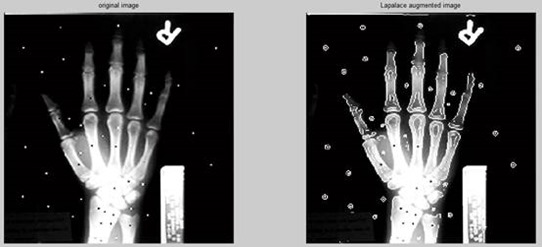

2. Edge composite enhancement

- The enhancement effects of the Sobel, Robert, and Prewitt operators are not very obvious, especially the Robert operator, because the edge points it extracts are too sparse and discrete;

- The enhancement effects of the Laplacian operator and the canny operator are both ideal. After superimposing the edges, the outline and edges of the entire hand are very clear. Intuitively, the effect achieved by the canny operator is better than that of the Laplacian operator. The most obvious thing is It’s the edge of your fingertips.